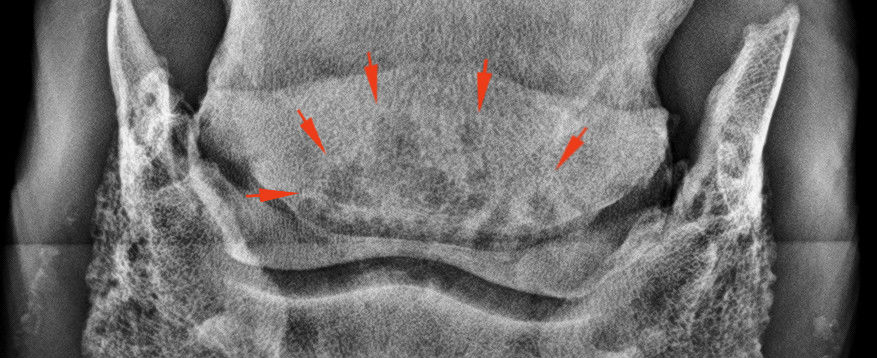

A nyírcsont vizsgálatára szolgáló un. oxspring felvétel. A nyilak a nyírcsontot mutatják.

Három ciszta a nyírcsont állományában.

Klasszikus „teniszütő” elváltozások.

A nyírcsont állomány szivacsossá vált a csontban zajló bomlási folyamatoktól.